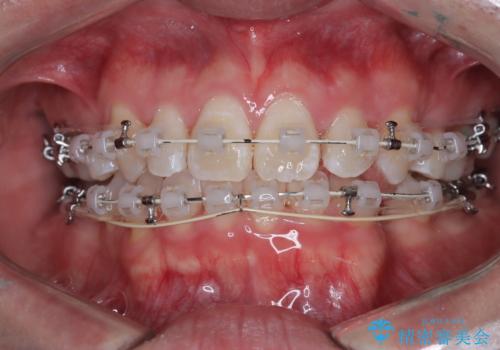

正中の改善と前歯の整列:抜歯を伴う矯正治療の症例

- 前歯のガタガタや正中の不整を改善するために、右上4、左上4、左下4を抜歯し、矯正治療を行いました。この治療により、見た目だけでなく、咬合のバランスも改善され、患者様の口腔内の健康が向上しました。

審美ワイヤー装置は、見た目を重視した矯正治療において非常に有効な選択肢です。患者様のニーズに応じた治療が可能で、美しい歯並びを目指すことができます。